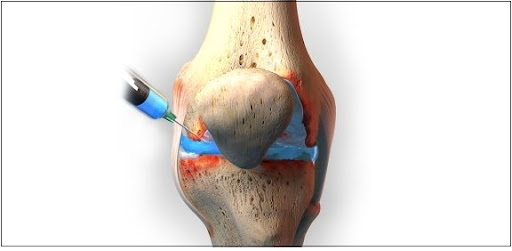

Eklem içi enjeksiyonlar

Kortizon enjeksiyonuna ek olarak, yapay eklem sıvısı olarak tabir edilen hyalorunik asit, PRP ( Platelet rich plazma), kök hücre, eksozomlar gibi her biri değişik etki mekanizmasına sahip ve değişik oranlarda etkinlikleri olan bir çok enjeksiyon seçeneği mevcuttur.